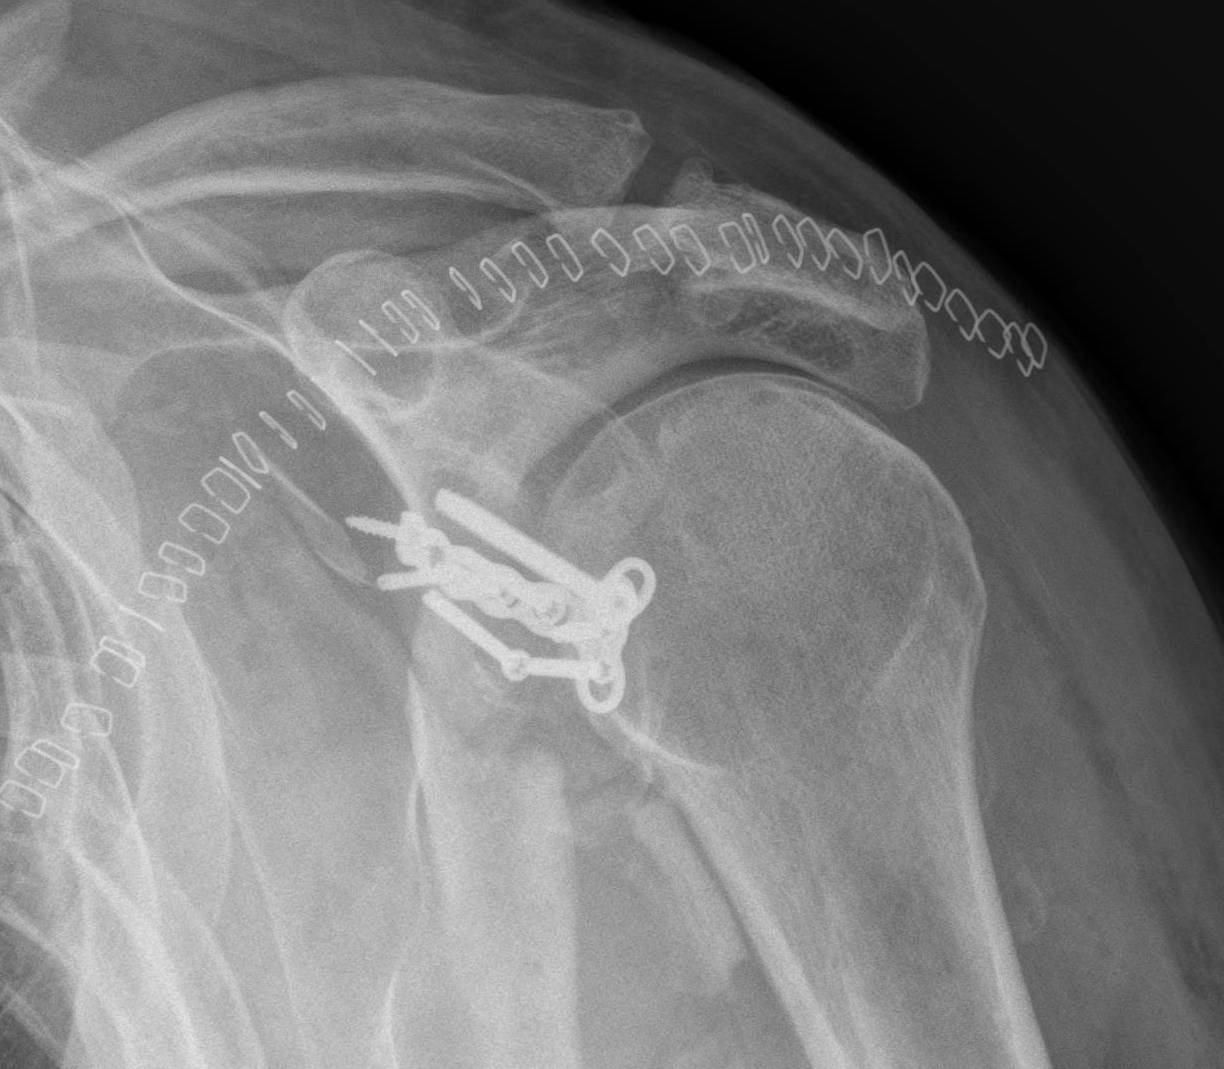

From onlinelibrary.wiley.com

Treatment of Chronic Anterior Shoulder Dislocation by Coracoid Scapula Bone Dislocation in these shoulder dislocations, the humeral head is displaced posterior to the glenoid fossa of the scapula. Shoulder dislocations can involve any of the three different joints that make up the shoulder. shoulder fractures most often involve the clavicle (collarbone), proximal humerus (top of the upper arm bone), or the scapula (shoulder blade). your shoulder joint is. Scapula Bone Dislocation.

From www.researchgate.net

(a), Xray images show right scapula and that distal clavicle is Scapula Bone Dislocation shoulder fractures most often involve the clavicle (collarbone), proximal humerus (top of the upper arm bone), or the scapula (shoulder blade). Shoulder dislocations can involve any of the three different joints that make up the shoulder. in these shoulder dislocations, the humeral head is displaced posterior to the glenoid fossa of the scapula. shoulder dislocation (correctly termed. Scapula Bone Dislocation.